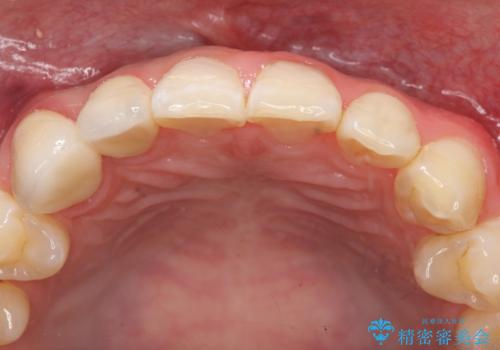

- 右上2、3番目の歯の色・形が気になるといらっしゃった方の症例です。

古い樹脂を除去後、オールセラミッククラウンによる補綴を行いました。

今回用いたオールセラミッククラウンは、ジルコニアフレームという白い素材の上にセラミックを盛っているため審美性が非常に高いのが特徴です。

またジルコニアは人工ダイヤモンドの材料にも使われているほど高い強度を持っており、そのためオールセラミッククラウンは審美性だけでなく、奥歯やブリッジの補綴も可能とするクラウンです。